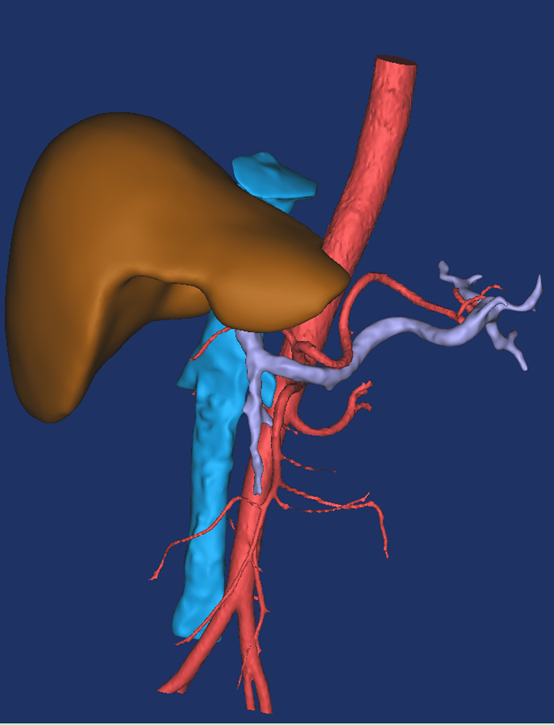

最后建模出来的效果:

正面图(肝脏+动脉+门静脉+腔静脉)                                反面图                                                          透视图